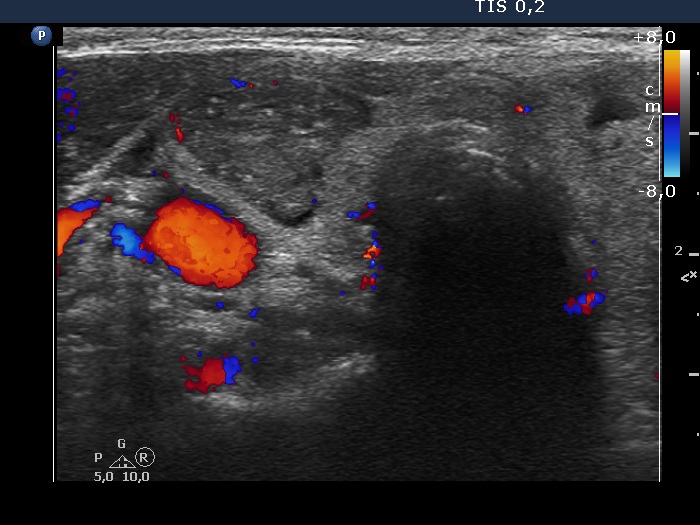

Right lobe, longitudinal scan

Right lobe, transverse scan, color Doppler mode. The vascularization is scanty.